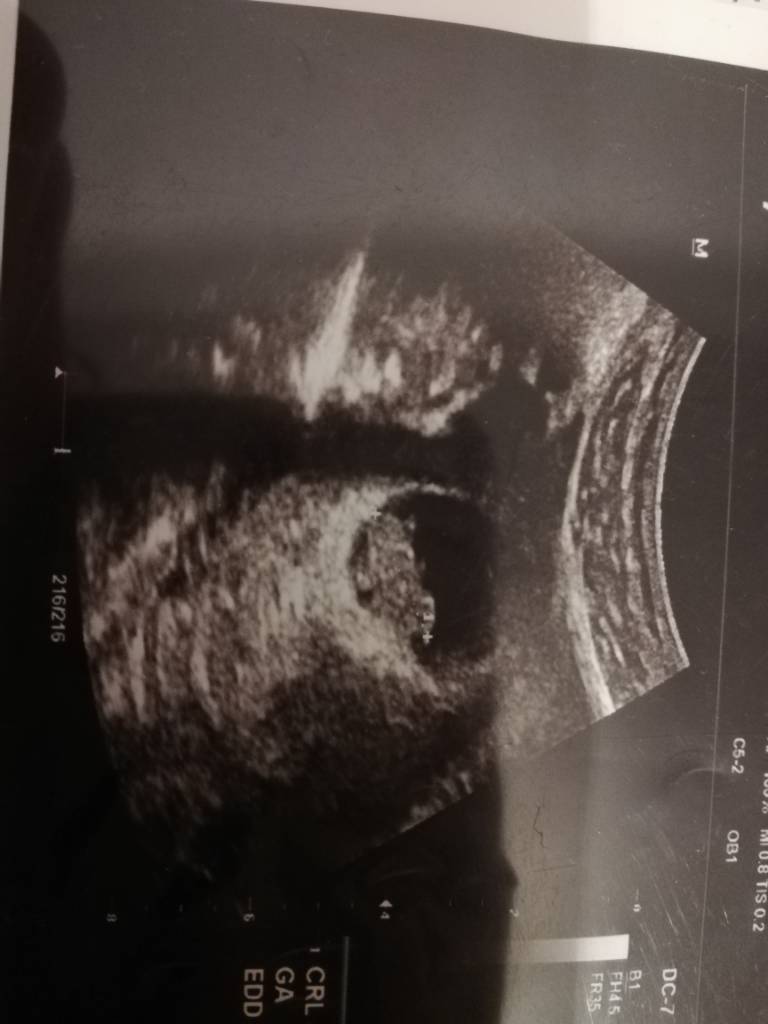

To razem z @fa.solka mamy ten sam termin. Ja wcześniej pisałam Wam, że mdłości odeszły i się martwię.... Wieczorem zaczęło się od nowa, także znów się cieszę[emoji33][emoji16].Jestem po wizycie wg usg 8.3 czyli 3 dni mniej niż z miesiączki. Ale jestem już spokojniejsza rośnie i serduszko bije. Ma 19.5 mm. No i niestety mam za wysoki cukier, będę robić test tolerancji glukozy. Kolejna wizyta za 4 tygodnie. Zobacz załącznik 1229115